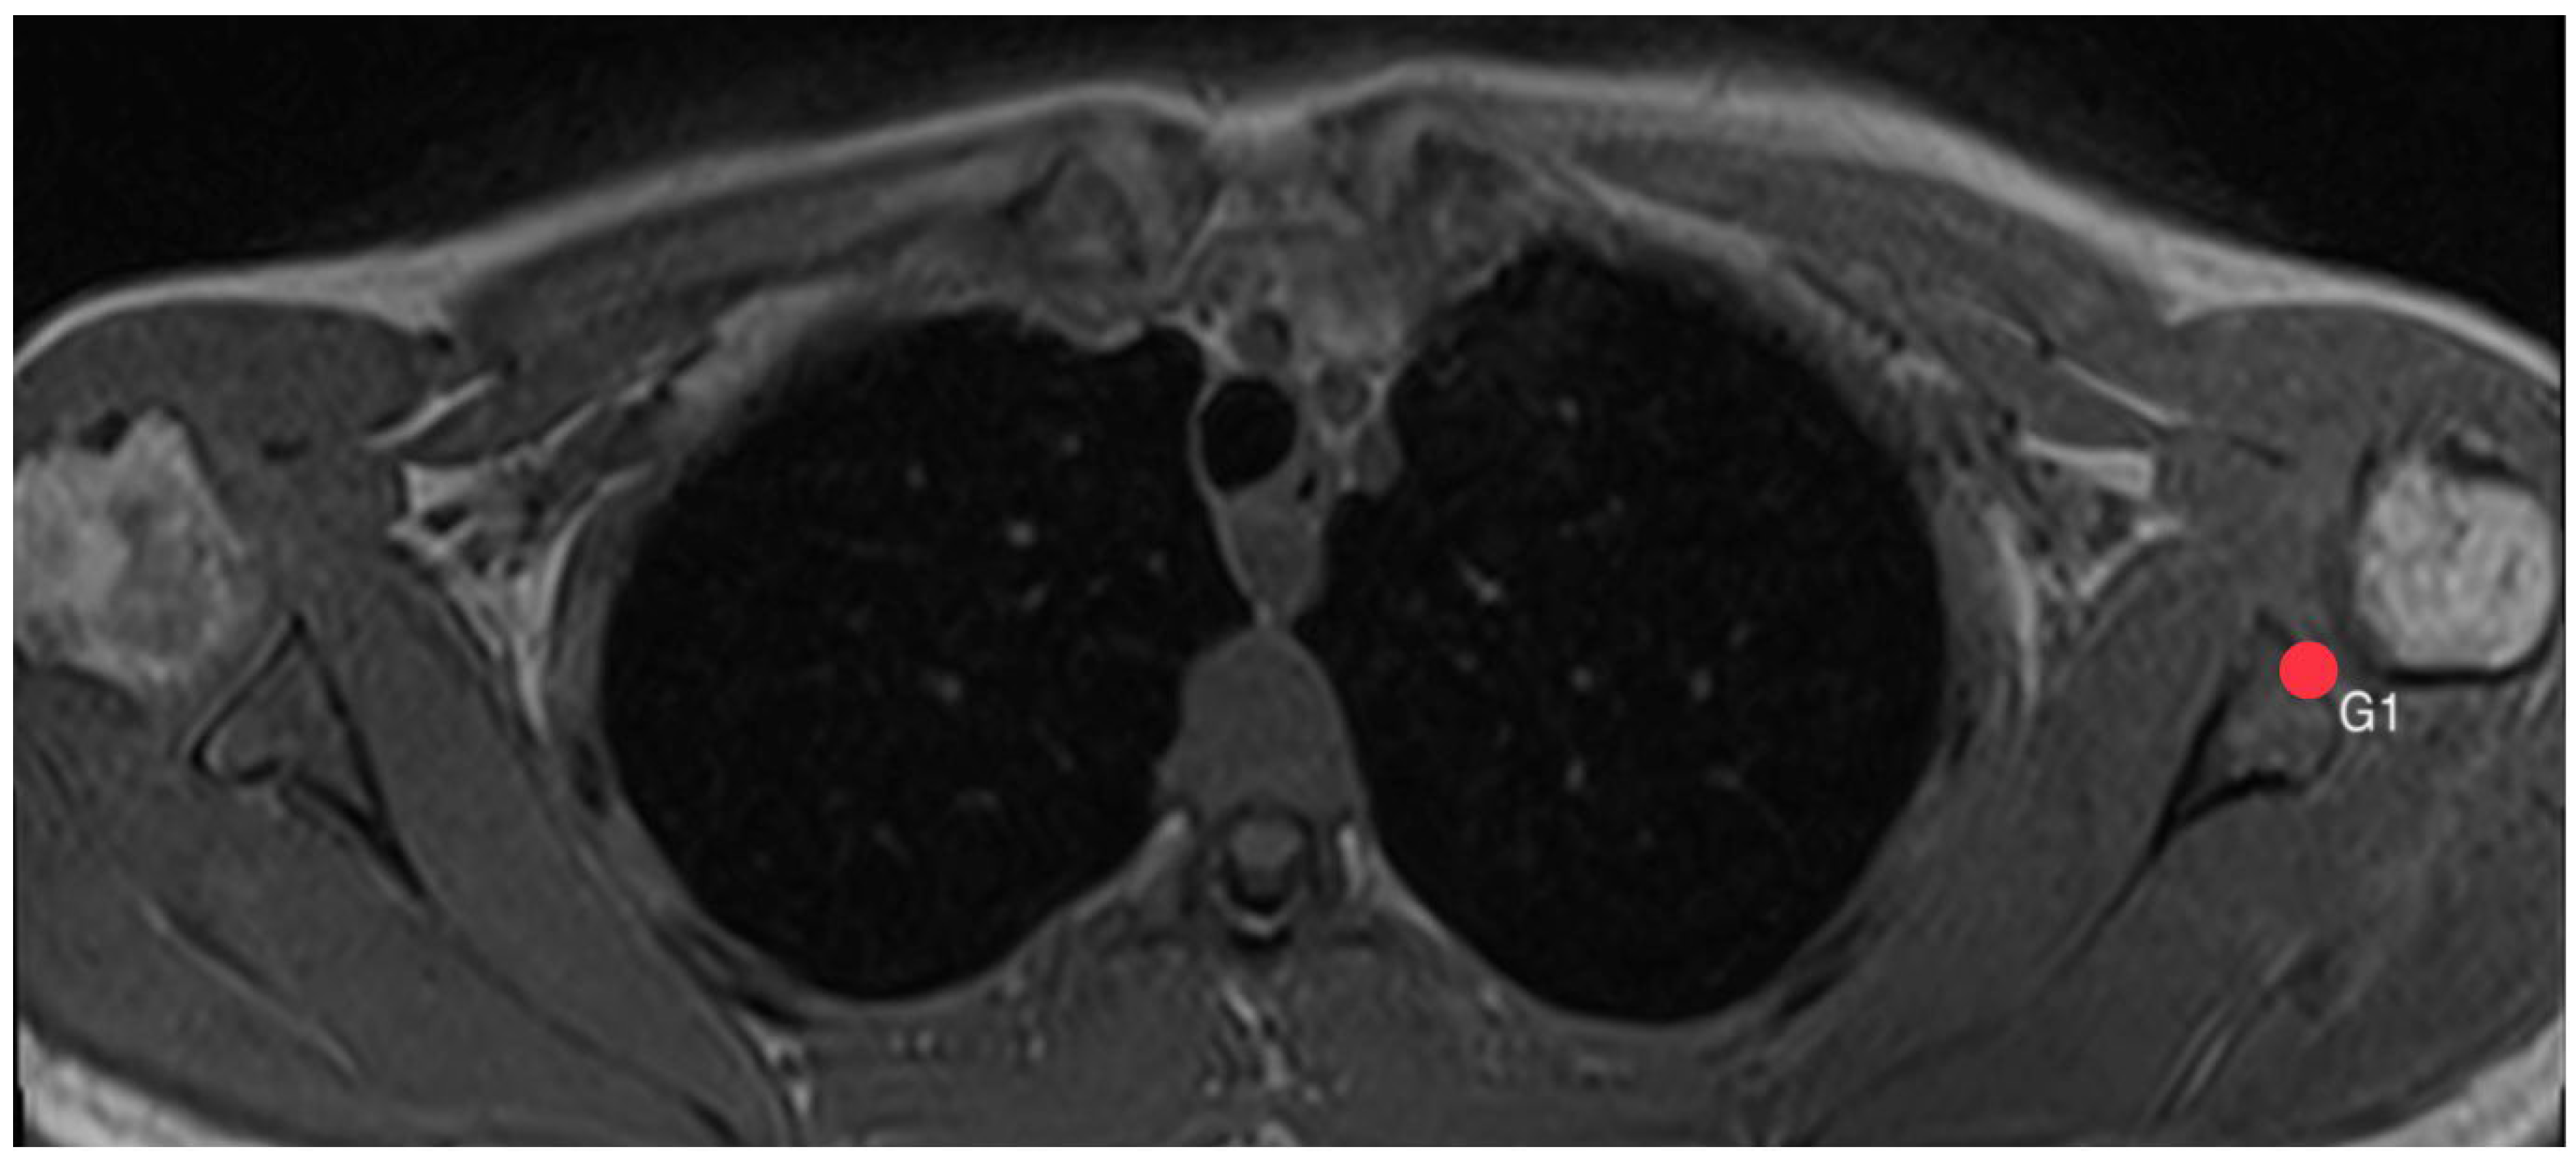

2.4. Acromion Tilt (Figure 6)